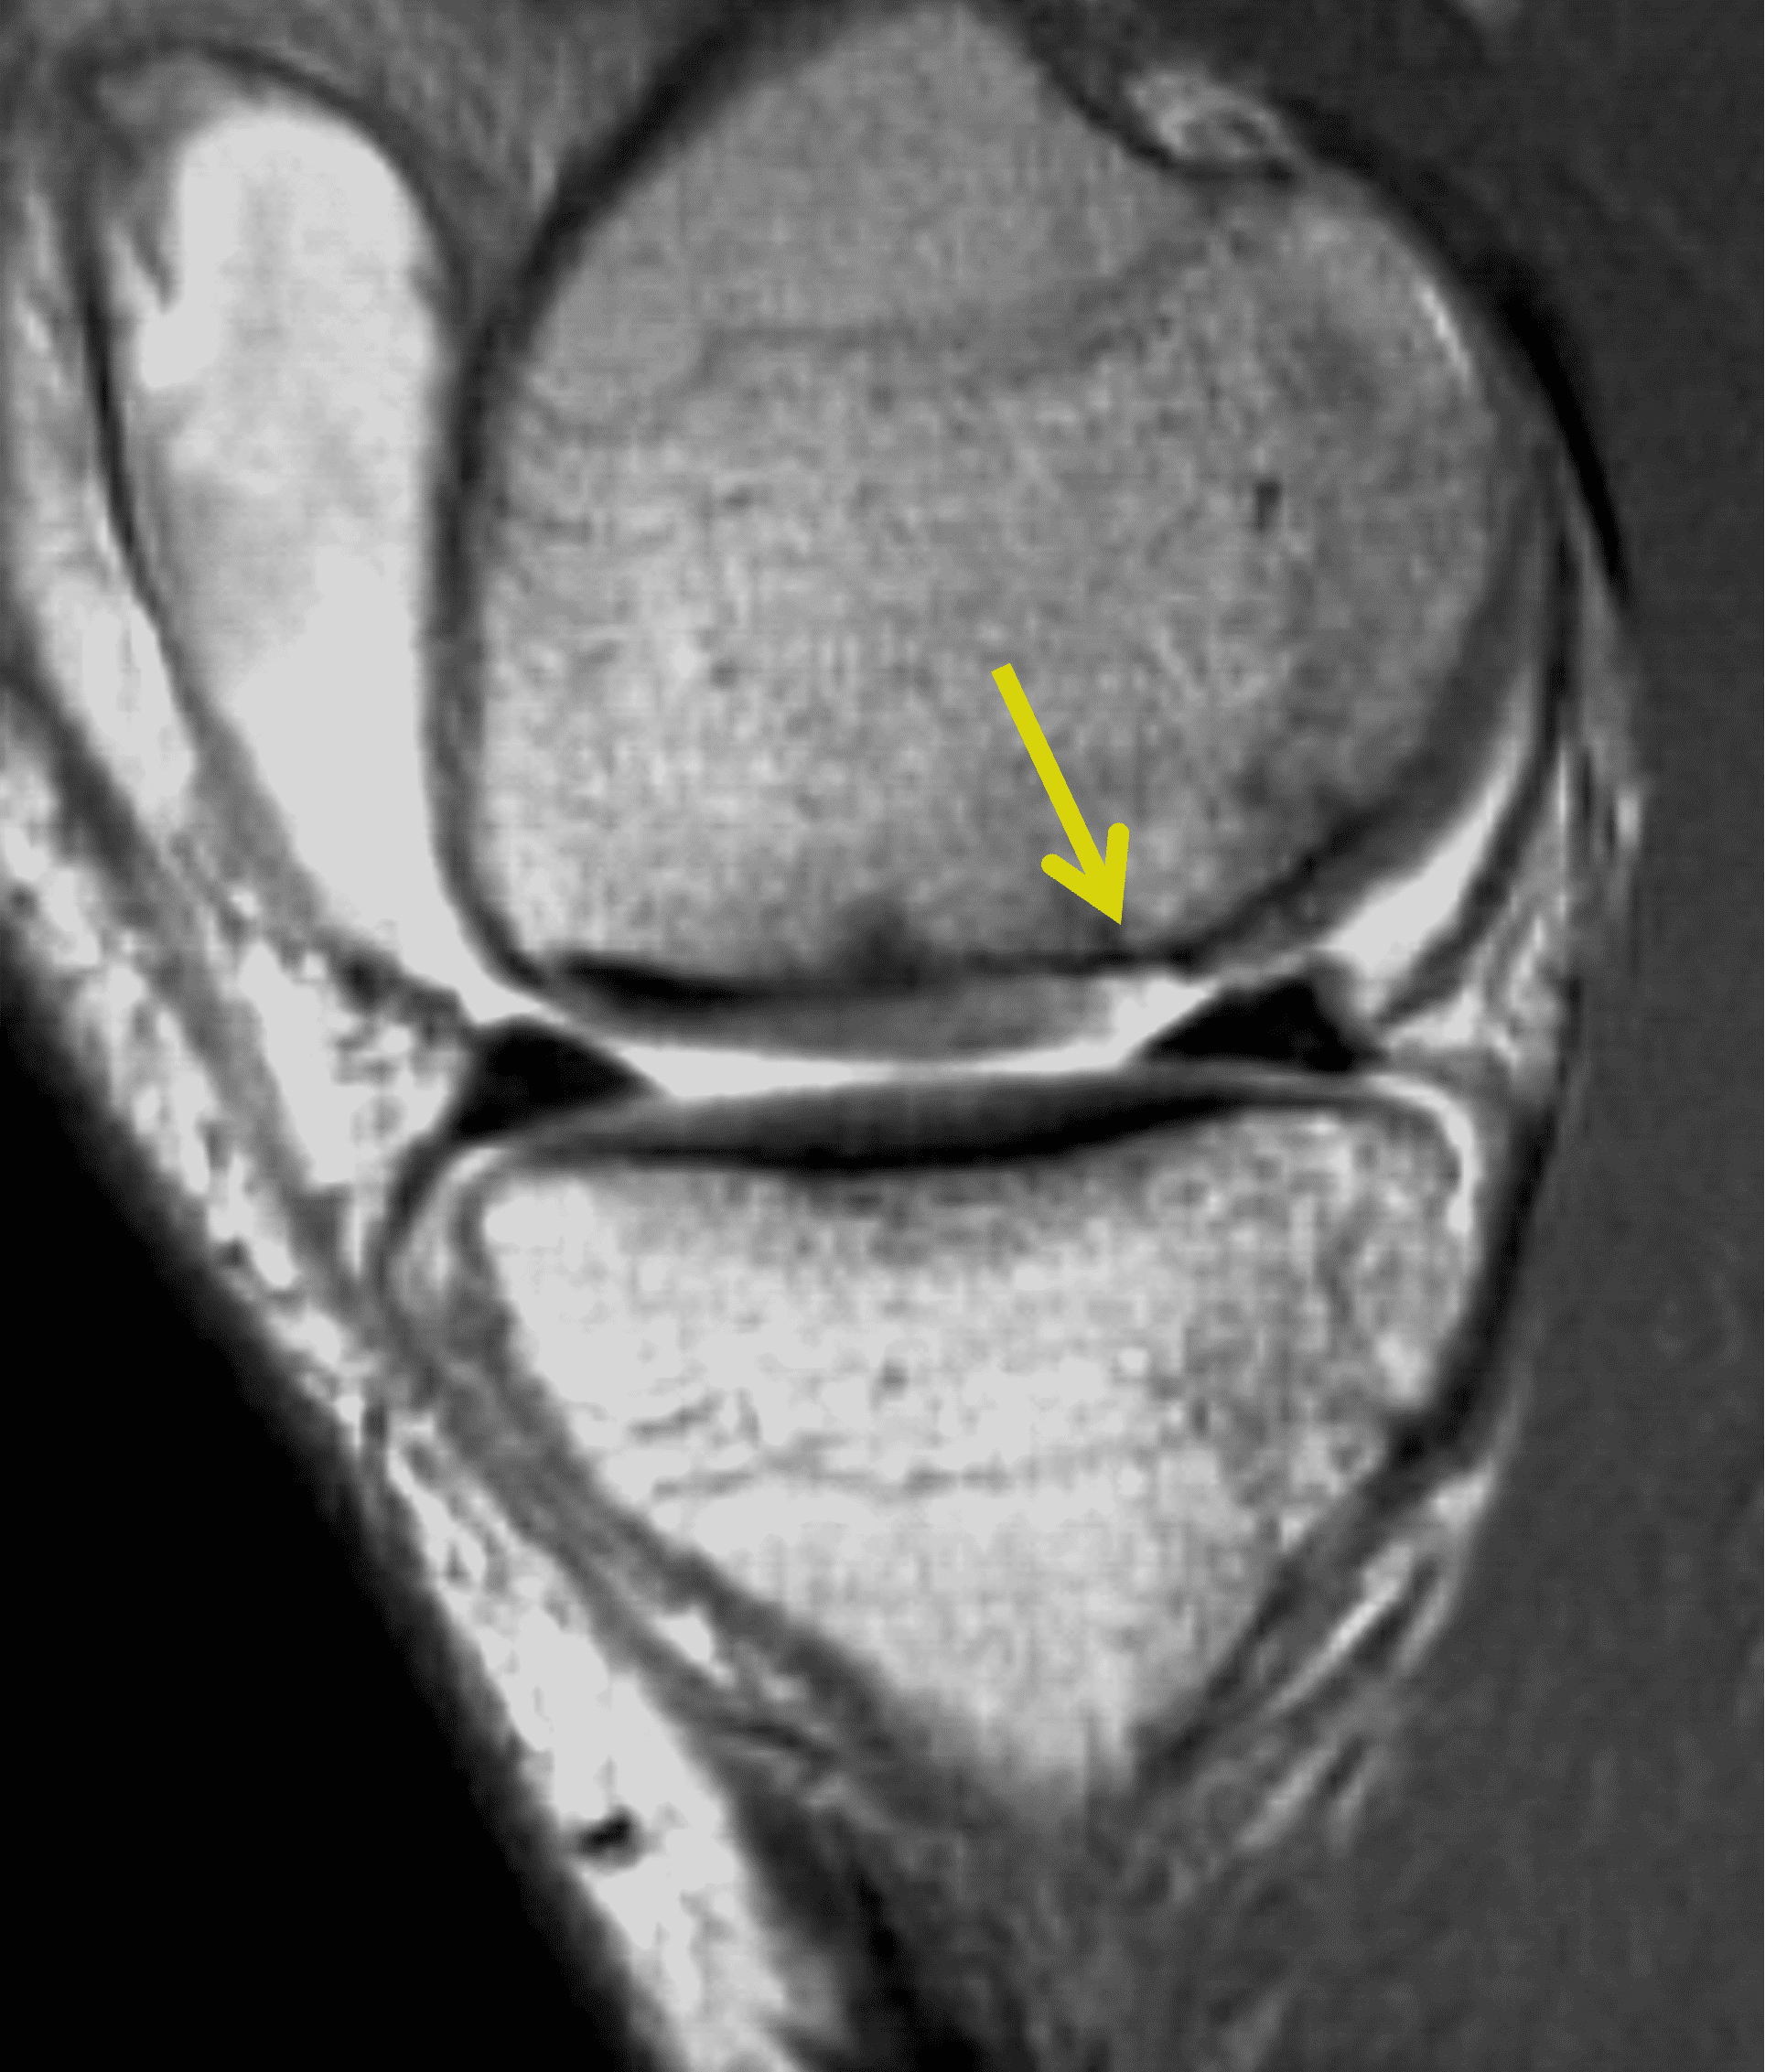

Because the thickness of the transplanted cartilage may differ from that at the recipient site, a step-off in the subchondral bone plate can be visible at the junction between the lesion and graft as a normal finding (Figure 14). The articular surface of the graft, however, should be congruent and flush with the surrounding cartilage on MRI. Marrow edema surrounding the graft is common in the first 3-9 months. The signal intensity within the transplanted cartilage can be variable, and like marrow changes, may take up to 3 years to normalize.29 Successful grafts will show incorporation of the transplanted bone with the surrounding bone (Figure 15). Cyst developmental at the base of graft may be a clue to poor incorporation (Figure 16) but can also be an incidental finding. Other than bone integration and surface congruence, most MRI findings have a weak correlation with outcomes. Osteonecrosis of the graft is a rare complication characterized by low signal intensity in the graft on T1-weighted images and lack of intravenous enhancement; however, graft osteonecrosis does not necessarily correlate with outcomes.24 Over time, osteochondral autografts may fail through development of degenerative arthritis with fissuring of the articular surface and cartilage loss (Figure 17).

Figure 14: Healing osteochondral autograft reconstruction for a patellar chondral defect. (14A) Sagittal proton density-weighted image 6 months after OATS shows a step-off between the subchondral bone plate of the graft (yellow arrow) and adjacent cartilage (black arrows). In this case the donor articular cartilage was thicker compared to the recipient site. (14B) Axial fat-suppressed fluid-sensitive image shows a congruent articular surface across the graft and surrounding cartilage (red arrows) despite the mismatch in the subchondral bone plates. High signal intensity in the grafted cartilage and marrow edema in the grafted bone can be normal findings up to 3 years after the procedure. A second look arthroscopy found that the graft was healing and confirmed a congruent articular surface.